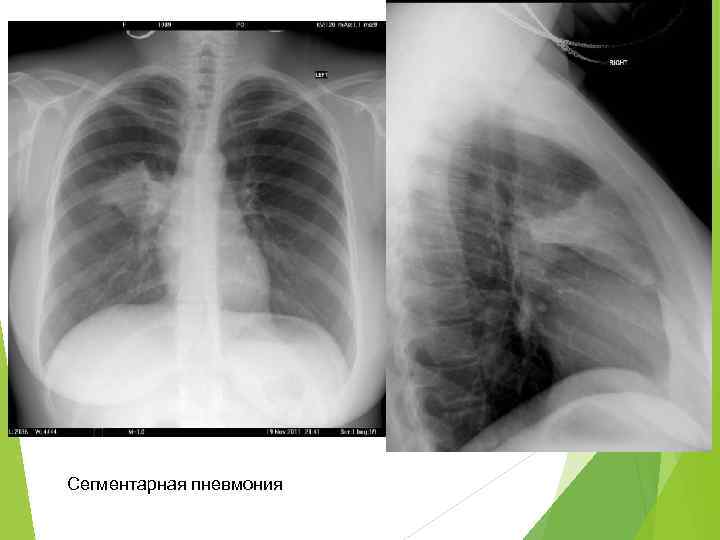

Рентгенодиагностика бронхопневмонии: Советы и примеры

Раздел: Альбом открытий